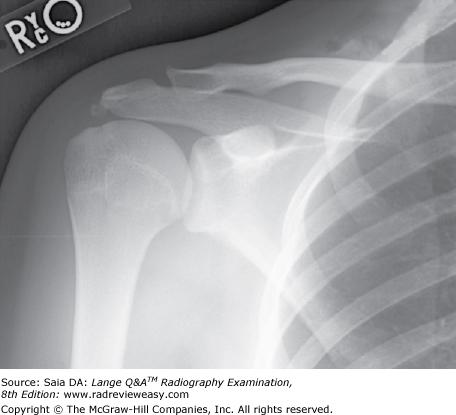

Which of the following statements is (are) true with respect to the radiograph shown in the Figure below?

- The acromion process is seen partially superimposed on the third rib.

- This projection is performed to evaluate the scapula.

- This projection is performed to evaluate the acromioclavicular articulation.

2 only

What projection was used to obtain the image seen in Figure 2–41?

AP, external rotation

What should be done to better demonstrate the coracoid process shown in Figure 2–22?

A Use a perpendicular CR.

B Angle the CR about 30 degrees cephalad.

C Angle the CR about 30 degrees caudad.

D Angle the MSP 15 degrees toward the affected side.

Angle the CR about 30 degrees cephalad